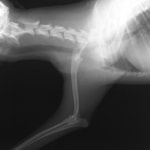

症例:トイプードル 9カ月齢

3ヵ月前より左前肢の跛行が認められるとのことで、来院されました。整形外科学的検査において、患肢の肘関節・肩関節重度の伸展制限が認められました。Xray検査において、左肩関節の内方脱臼、および肩甲骨関節窩の低形成と上腕骨頭の変形が認められました。

数か月に及ぶ慢性脱臼のため、関節面の低形成・摩耗のため整復手術による適切な再建は困難と判断し、切除関節形成術を実施しました。

術後3週間頃より、負重状態、歩行が改善しました。

切除関節形成術は、疼痛を引き起こす関節面を除去し、線維性偽関節の形成により患肢の機能改善を促す救済的手術です。術後のリハビリテーションの実施により、関節の可動域や患肢の筋肉量は改善され、生活の質は向上します。また本症例のように、慢性脱臼だけでなく、重度の骨関節炎症例にも実施することがあります。